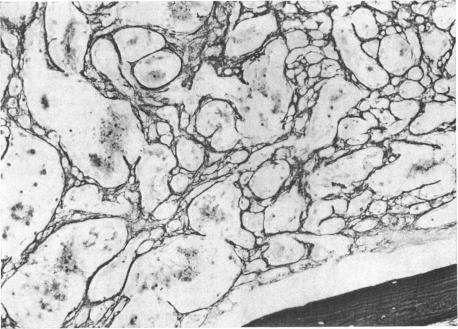

Two cases of angiosarcomas of the heart are described. In one the tumour, which arose from the right atrium, was demonstrated during life by angiography. In the other, diagnosed only at necropsy, the tumour arose from the right ventricle. Both cases illustrate many of the typical features of this rare tumour and the difficulties of antemortem diagnosis.

本文描述了两例心脏血管肉瘤。其中一例肿瘤起源于右心房,生前通过血管造影得以证实。另一例仅在尸检时确诊,肿瘤起源于右心室。这两例病例均体现了这种罕见肿瘤的许多典型特征以及生前诊断的困难。